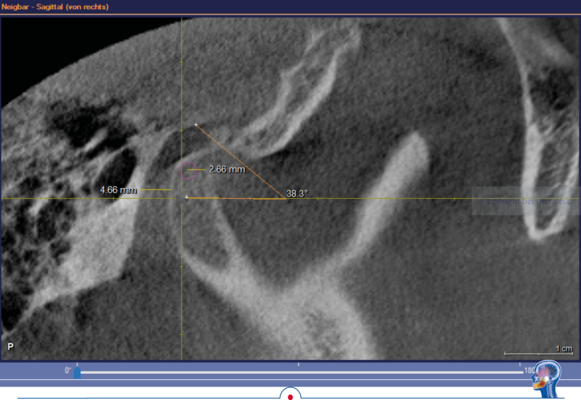

Grundsätzlich ist es logisch, dass die habituelle Okklusion den Patienten in

seine jeweilige Kondylenposition „zwingt“. Das kann man sehr schön bei einer

DVT-Aufnahme erkennen, wenn diese ohne frontalen Aufbiss in habitueller Okklusion realisiert wird.

In dem DVT wird sichtbar, dass der linke Kondylus in habitueller Bisslage um

ca. 2,5 mm deutlich zu anterior positioniert ist. Ursache dafür ist der Zahnkontakt bei 26 und 36. Dieser Zahnkontakt zwingt den Unterkiefer linksseitig in die anteriore Kondylenposition. Wenn jetzt in diesem Gebiss eine klassische Handbissnahme für eine Zahnversorgung durchgeführt wird, wird diese „falsche Kondylenposition“ in den Artikulator übertragen.

In dem hier vorgestellten Fall wurden diese Parameter zusätzlich im DVT bestimmt. Die im DVT ermittelte sagitale Gelenkbahnneigung beträgt rechts 41,9° und links 38,3°. Die mit Centric Guide® 3D ermittelte Gelenkbahnneigung beträgt rechts 43,86° und links 38,03°. Damit weichen die beiden Werte rechts nur um 1,96° und links nur um 0,27° voneinander ab. Wenn man sich die Gelenkbahneinstellung im Vollwertartikulator anschaut, stellt man schnell fest, dass diese nur in 5° Schritten erfolgt.